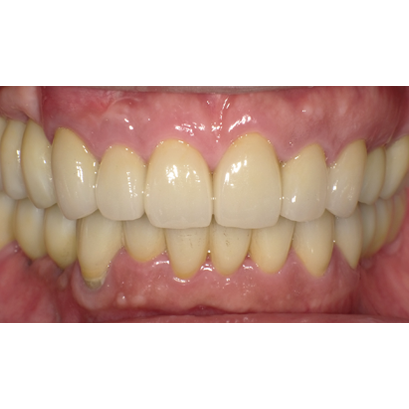

23.口腔内写真(2024年6月26日)

25.初診より18年経過(2024年6月26日)